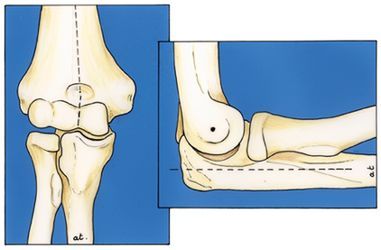

Technique Arthrolyse arthroscopique du coude - Intérêts et limites , Jérôme Pierrart Hôpital Avicenne, Assistance Publique-Hôpitaux de Paris, Université Paris 13, Sorbonne Paris Cité, Bobigny, France , Christian Dumontier Hôpital Saint-Antoine, Paris, France N°229 - Décembre 2013 ● 24 min de lecture

Technique Traitement arthroscopique de l'épicondylite latérale (tennis elbow) , Christian Dumontier Hôpital Saint-Antoine, Paris, France , V. Beauthier Hôpital saint Antoine - 75012 Paris N°197 - Octobre 2010 ● 25 min de lecture

Congrès - Compte rendu Epicondylalgies et épitrochléalgies , Ph. Bellemère Institut Montpelliérain de la Main et du Membre Supérieur, Clinique Clémentville, 25 rue Clémentville, 34070 Montpellier, France , B. Boisaubert , Bertrand Coulet CHU Montpellier - Hôpital Lapeyronie, Montpellier, France , F. Degez , Christian Dumontier Hôpital Saint-Antoine, Paris, France , C. Girault , Jacky Laulan Unité de Chirurgie de la Main, Hôpital Trousseau, CHRU de Tours, 37044 Tours, France , Y. Roquelaure N°193 - Avril 2010 ● 31 min de lecture

Mise au point Examen clinique du coude , Christian Dumontier Hôpital Saint-Antoine, Paris, France N°77 - Septembre 1998 ● 43 min de lecture